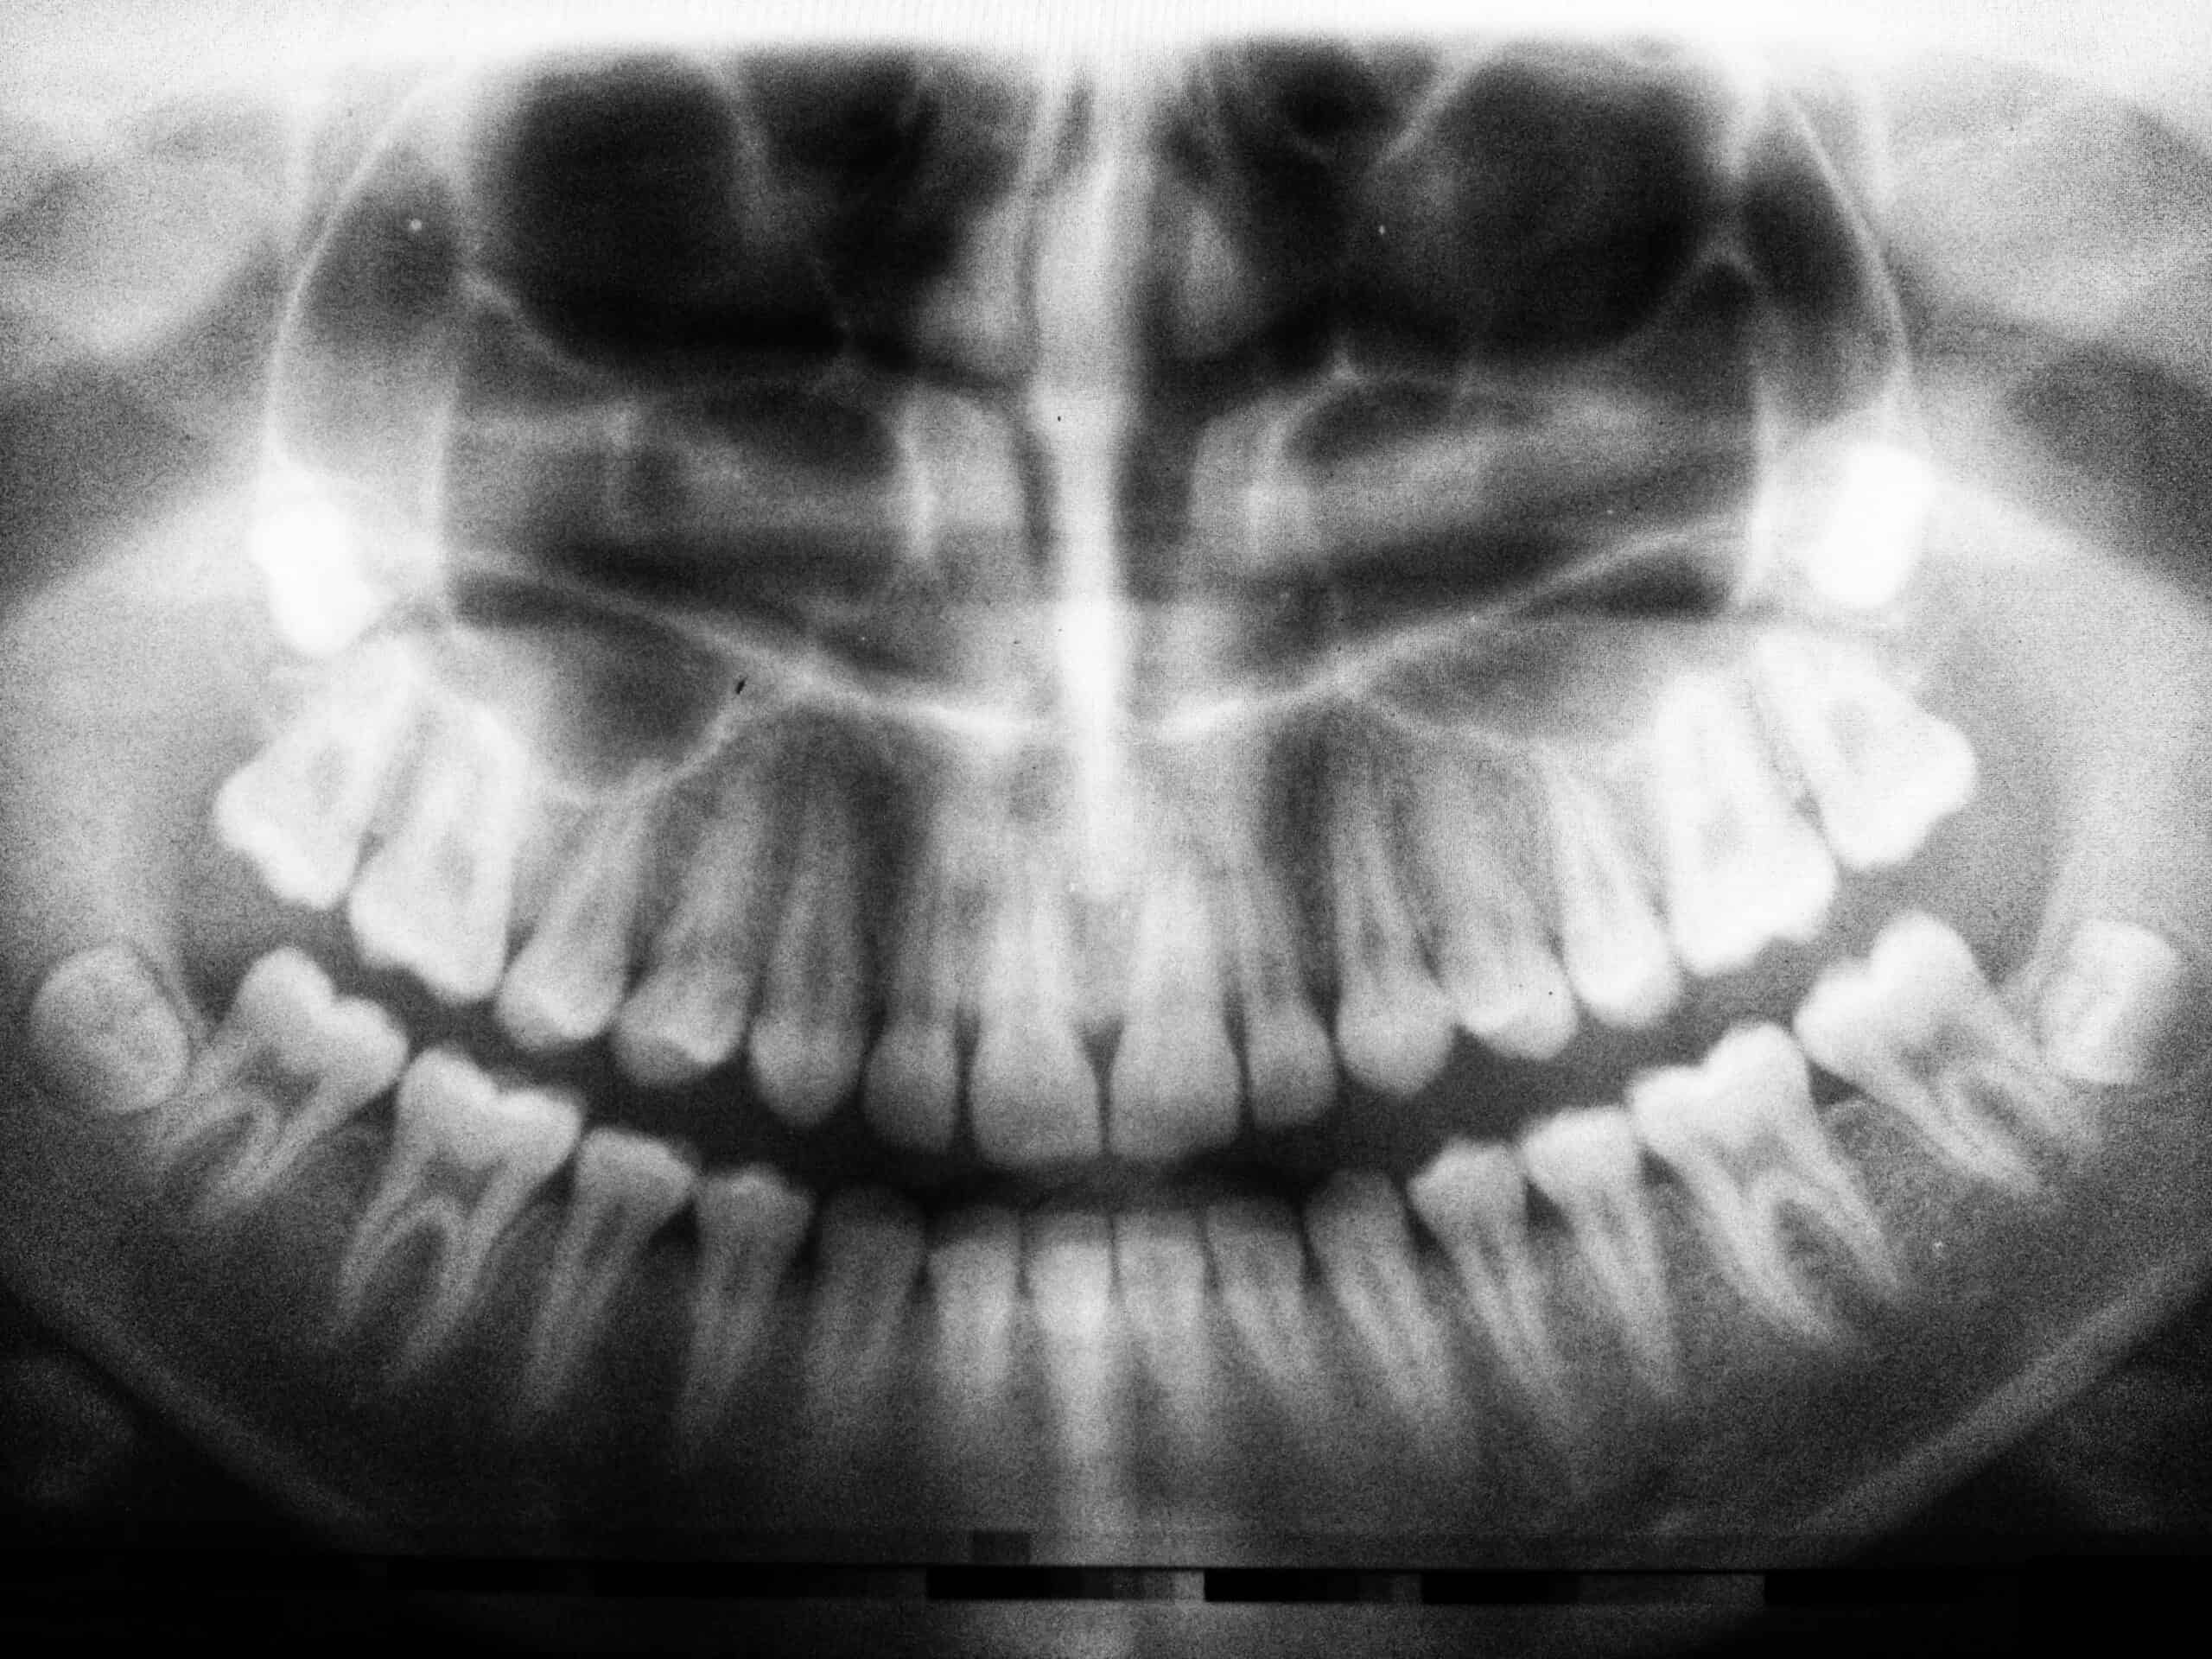

Do I Need A Root Canal Reddit . I truly think it’s the best. The decay is well into the nerve canal. I carefully researched the dentist i asked to do my root canal and ensured i used someone reputable who was recommended to. I'm surprised you don't feel pain but in time you will. I said no, and that i was lucky to have avoided a root canal, and she told me that it still might need a root canal in the future. If you cannot afford root canal treatment and decide to delay it, consider a few signs and symptoms that might help you identify the status of your tooth. I don’t consider it preventative or aggressive treatment. Asymptomatic irreversible pulpits is an indication for a root canal. I too recently read that other forum and its theory on root canals, and felt quite terrified. One would need to see an xray to make a clear diagnosis before deciding on root canal treatment (rct). Pain is the most common symptom. She said we could try a. I recently saw a new dentist (insurance change) who said i had a pretty big cavity and might need a root canal. Doing nothing will result in a big infection and tooth.